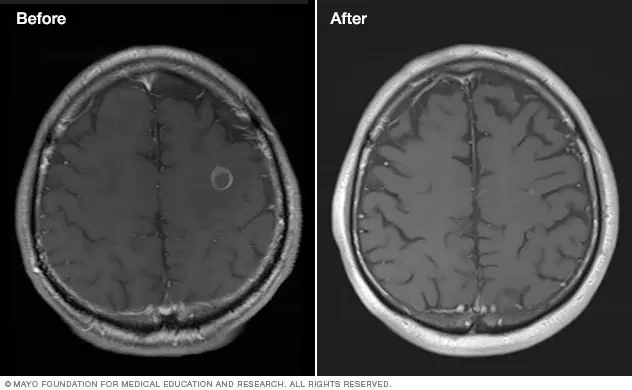

Patient selection relies on strict criteria, including lesion count and volume, yet current clinical guidelines are evolving to manage higher numbers of metastases.

Outcomes are often latent, with benign tumors shrinking over months or years post-exposure.

Historically, the evolution of brain tumor management has tracked with the miniaturization and accuracy of radiation delivery. Stereotactic radiosurgery has shifted from a novel intervention to a standard pillar of oncology, replacing whole-brain radiation in many contexts to preserve cognitive function and minimize collateral tissue damage. The current discourse within medical journals focuses not on whether SRS works, but on the optimization of fractionation protocols and the integration of salvage treatments for metastatic failure. The 90% deficit suggests that the future of the field is less about finding new physics and more about solving the geometry of healthcare access.